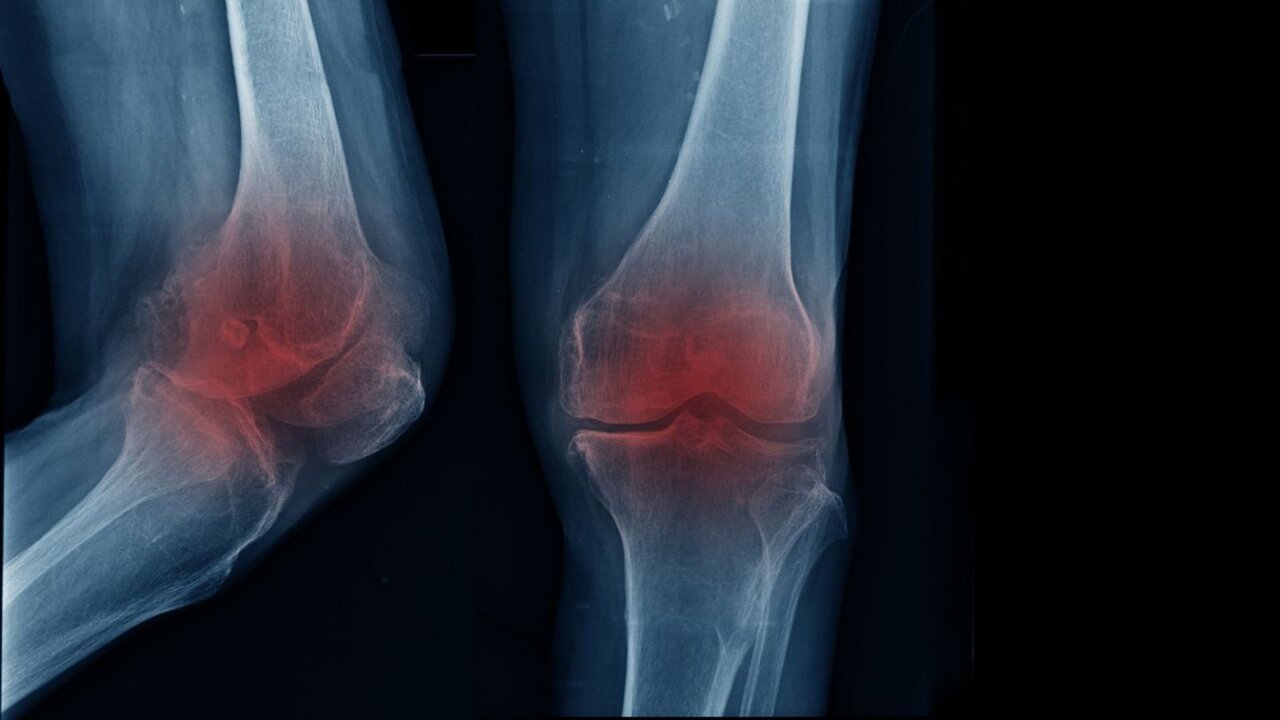

به گزارش خبرگزاری ایمنا، مفصل زانو یکی از پیچیدهترین و پرکاربردترین مفاصل بدن است که از غضروف، استخوان، رباط و مایع سینوویال تشکیل شده است؛ غضروف زانو به عنوان پوشش محافظ استخوانها، وظیفه کاهش اصطکاک و جذب فشار ناشی از حرکات روزمره را دارد و با افزایش سن، این غضروف به مرور نازک میشود و خاصیت ارتجاعی خود را از دست میدهد که زمینهساز آسیبهای جدی از جمله آرتروز میشود و استفاده مداوم از زانو در زندگی روزمره مانند راهرفتن، دویدن یا بالا رفتن از پلهها، این مفصل را در معرض ساییدگی و فرسایش قرار میدهد.

حسین اکبری اقدم، متخصص ارتوپدی و فوق تخصص جراحی زانو و عضو هیئت علمی دانشگاه در گفتوگو با خبرنگار ایمنا با بیان اینکه مفصل از غضروف تشکیل شده است، اظهار کرد: مفصل زانو یکی از مفاصلی است که در زندگی بسیار مورد استفاده قرار میگیرد و با افزایش سن، غضروف مفصل ساییده میشود و فرد دچار آرتروز زانو یا ساییدگی مفصل میشود.

وی با بیان اینکه زمانی که غضروف مفصل زانو از بین برود، فرد دچار آرتروز میشود، افزود: آرتروز زانو دلایل مختلفی دارد که از جمله آنها میتوان به تصادف و ضربه و روماتیسم اشاره کرد؛ به طور کلی، علل بروز آرتروز، علل شناخته شدهای نیست و زمانی که عوامل خطر با یکدیگر ترکیب شود، فرد دچار آرتروز زانو میشود.

متخصص ارتوپدی و فوق تخصص جراحی زانو و عضو هیئت علمی دانشگاه با بیان اینکه درد مهمترین نشانه آرتروز زانو به شمار میرود، تصریح کرد: در ابتدا بیمار هنگام حرکت درد را احساس میکند و پس از آن، در صورت ساییدگی بیشتر غضروف مفصل زانو، بیمار ممکن است درد را حتی هنگام استراحت نیز احساس کند.